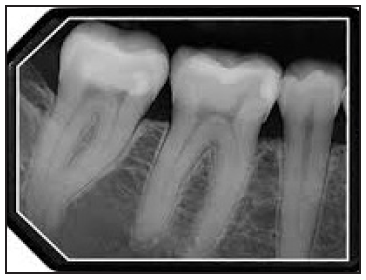

Bitewing images are parallel images because the receptor is positioned parallel to the long axis of the teeth and the beam is perpendicular to the receptor as in Figure 60. A bitewing tab is utilized to stabilize the receptor as the patient bites together.

Beam Angulation and Receptor Holding Devices

Bitewing radiographic images are usually exposed with an indicated vertical angulation of +10 degrees (tube head points down for positive (+) angulation). This angulation provides an acceptable compromise for the differences between the long axis inclinations of the maxillary and mandibular teeth. Horizontal angulation is aligned with the direction of the contact, and the central ray is directed between the contacts of the teeth to be radiographed. Horizontal angulation is achieved when the central ray of the x-ray beam is directed specifically between the contacts of the teeth to be radiographed.

The interproximal examination may be done using a special type 3 bitewing receptor but is preferably achieved by using type 2 receptors fitted with a tab. (Figure 61) There are also receptor holding devices available that support the receptor as well as provide an external reference for positioning the tube head. The patient stabilizes the receptor by gently biting together on the manufactured tab or on the holding device.

Tube head position is illustrated in Figure 62, and a sample set of bitewing radiographic images are illustrated in Figure 63.